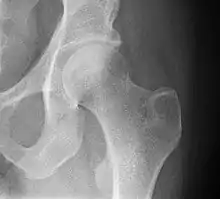

Переломи шийки стегна часто трапляються в літніх людей, частіше серед жінок, нерідко причиною тому є остеопороз. Також виділяють кілька різновидів переломів тазових кісток, що часто стаються під час дорожніх аварій.

Рентгенографія лівого кульшового суглоба (норма).